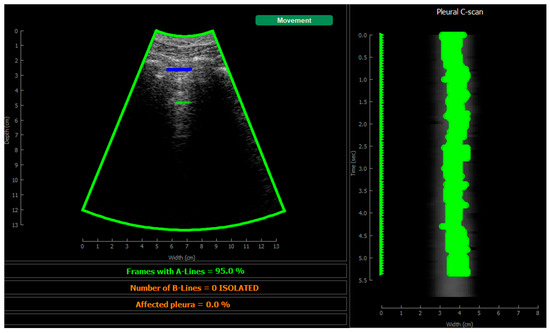

2.5.4. Visualization

3.2. Real-Time Implementation Results